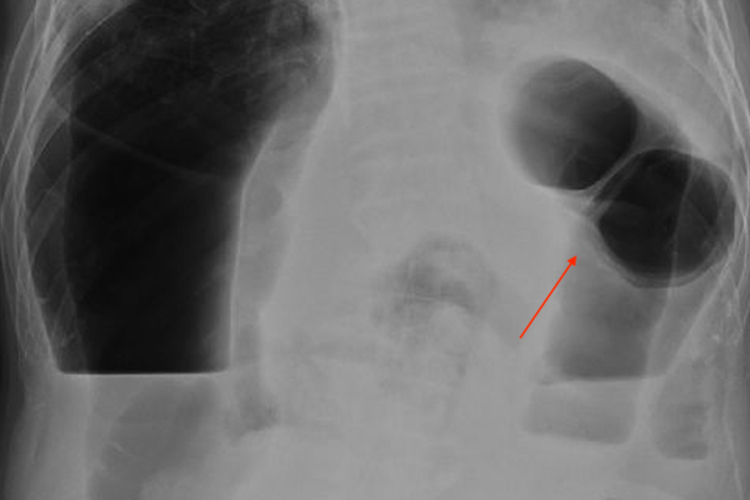

显示出肠腔内气体影,可见气胀肠样和液平面,也可在空肠黏膜的环状皱襞呈鱼肋骨刺状,或见结肠扩张、阶梯状的液平面,常提示小肠梗阻。如果是结肠梗阻时胀气位于腹部周边,显示结肠袋形。而显示“同心圆”X线征象时,则考虑肠套叠。

可显示扩张的肠曲,并可见多个肠腔内气液平面。如果肠管互相融合成团,或与腹壁相连,提示为粘连性肠梗阻。如有肠套叠,则可显示出典型CT征象,出现三层肠壁征。